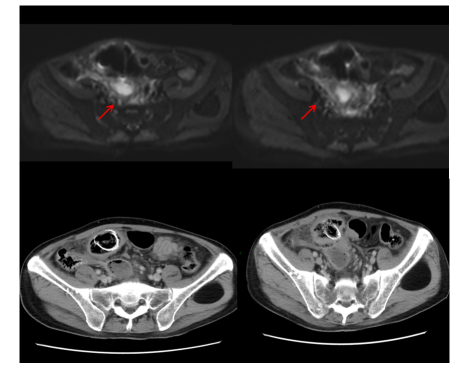

目前诊断:乙状结肠腺癌伴肝转移(cT3N2M1a IVA期) NRAS p.Q61L突变,TMB 6.2,MSS;中度贫血;双肺多发结节,转移待排(图7)。

目前诊断:乙状结肠腺癌伴肝转移;肝动脉内钇90放射治疗后;中度贫血;双肺多发结节,转移待排(图12)。

CEA、CA19-9略微升高(图17),肝脏多发转移瘤较前增多、增大(图15/16),双肺结节较前增多、增大(图14),评估为PD。

图14. 2025年2月25日CT:双肺结节,较2024年12月27日CT增多、增大